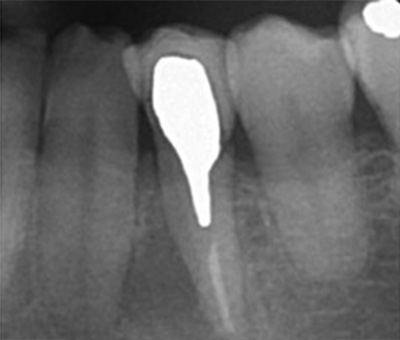

実際のケースを

こちらのレントゲン写真を見てください。どちらかの歯医者さんで神経を取っています。根管に入れる薬は白く映ります。赤矢印部分です。一番右側が模式図ですが、青い部分が薬、根っこの先の赤点が化膿している部分です。

薬がほとんど入っていないのがわかります。黄矢印部分です。青矢印まで薬が入らないといけないのですが、全く入っていません。その結果、根っこの先が黒くなっています。膿が貯まって化膿すると黒く写ってくるのです。

別な歯科医院で治してもらいました。薬が根の先まで入っているのがわかります(黄矢印)。 根尖の黒い影が消失しています(赤矢印)。骨が再生すると白く写るようになります。

ガッタパーチャポイントは、理想的には歯根(シコン)の先ピッタリが良いと言われています。

上の図にあるように神経の管に入れる薬が根尖(コンセン)まで入っていなかったり、途中までしか入っていなかったり、薬がスカスカだったりするとその空間にばい菌が繁殖して感染を起こします。

薬が真ん中までしか入っていないため、膿が貯まっている。

薬が根尖までしっかりはいっていない。

化膿している